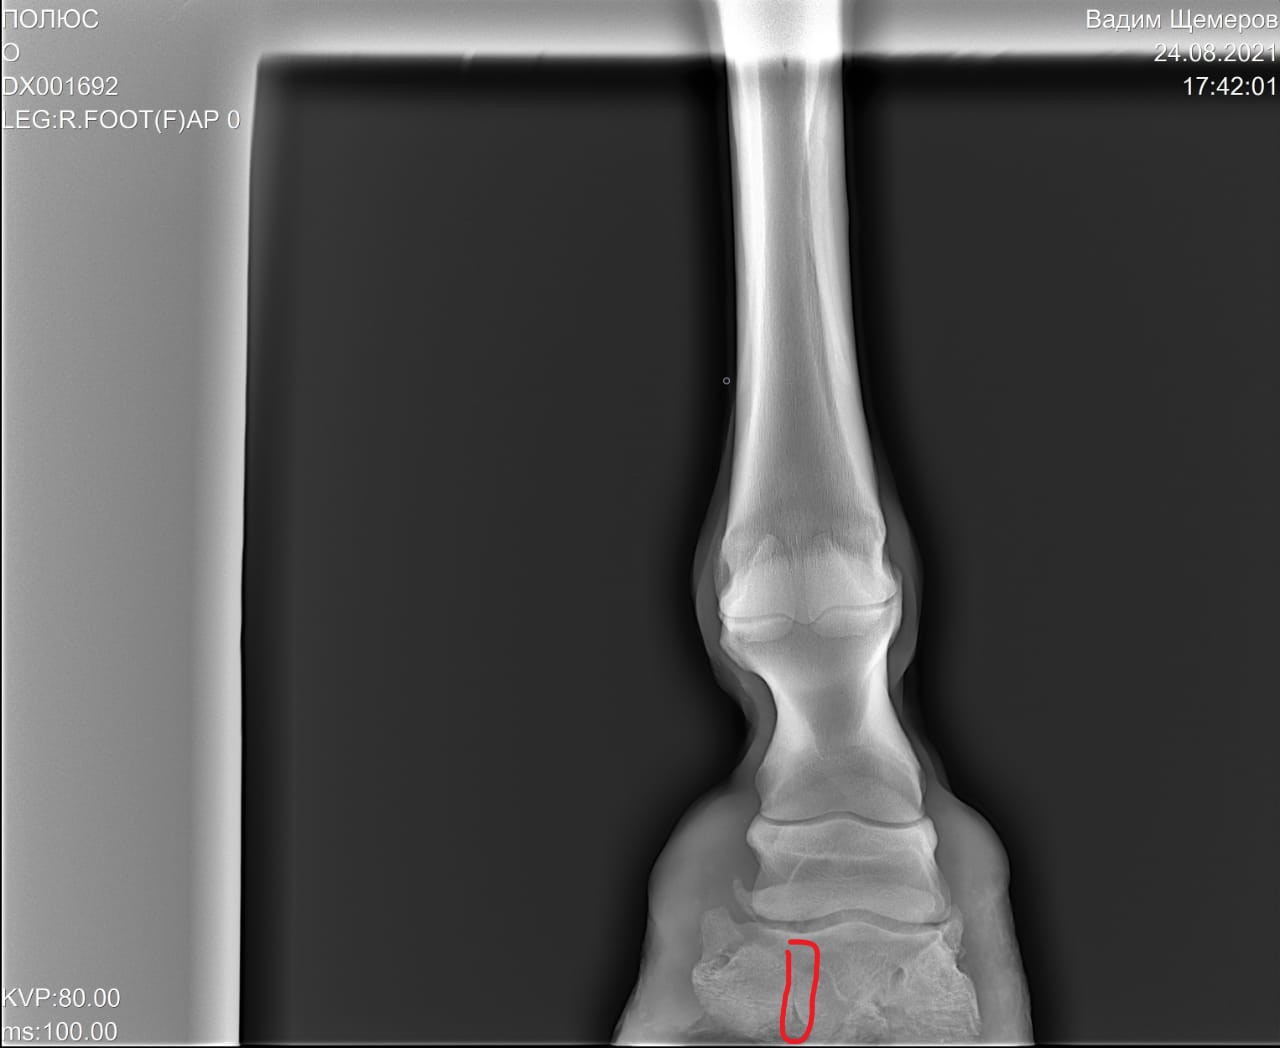

На рентгеновских снимках выявлено:

1) остеохондроз и чип в области путового сустава правой грудной конечности.

2) Старый перелом и изменение конфигурации края челночной кости с переостальной реакцией этого края.